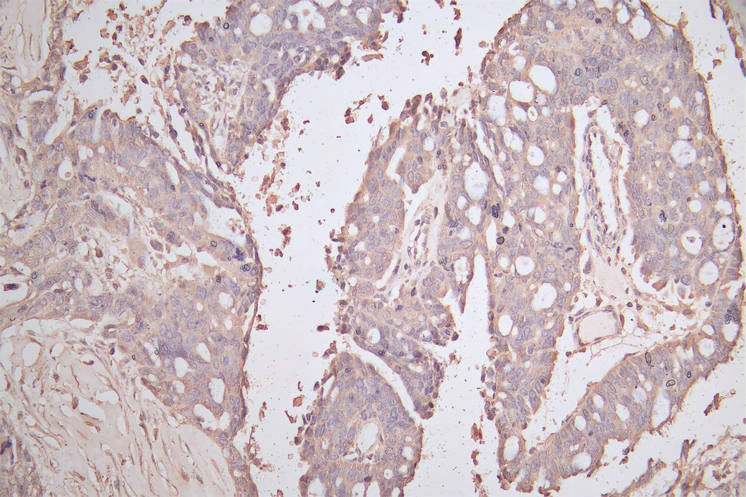

華美生物提供CDH1重組蛋白、抗體及ELISA試劑盒產(chǎn)品,助力您進(jìn)行相關(guān)機(jī)制研究及靶向藥物開發(fā)。